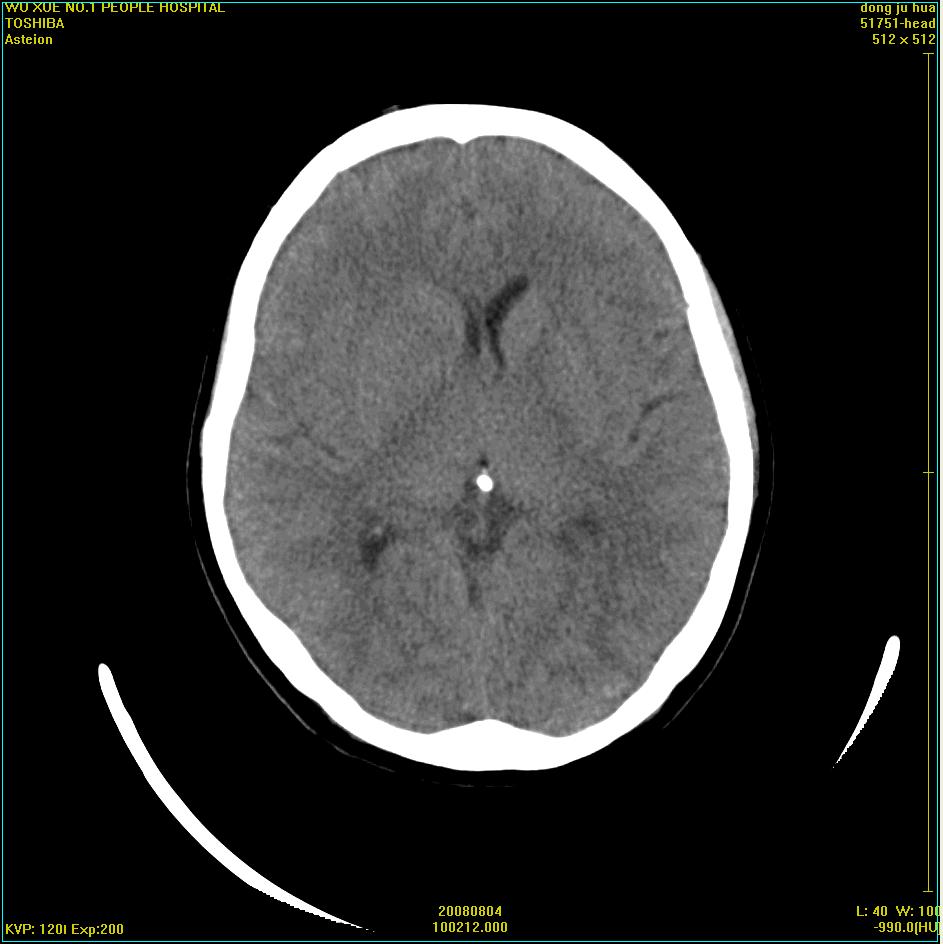

患者,女,45岁。四年前在我院做ct诊断为右侧桥小脑脚区三叉神经鞘膜瘤,已做手术。今复杳。请大家看看

三叉神经鞘膜瘤术后

考虑三叉神经鞘膜瘤术后复发并瘤体内出血。

三叉神经鞘膜瘤术后复发并瘤体内出血

考虑慢性扩张性血肿吧!请大家再看看,发表高见!

考虑:三叉神经鞘膜瘤术后复发并瘤体内出血。支持!

四年前做的手术,为什么大家不考虑慢性颅内血肿呢?

考虑慢性颅内血肿?症状体征有多少?能否发上?